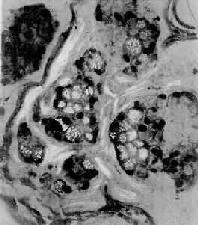

4.粘液(mucoid carcinoma)呈腺样结构或单纯结构,细胞胞浆内出现大量偏酸性粘液,常将胞核挤压于细胞浆之一侧,形似戒指,故称之为印戒细胞(signet-ring cell)(图10-19)。粘液的恶性度高。此型因组织含大量粘液,肉眼上呈半透明的胶冻状故也称胶样(colloid carcinoma)。

图10-19 粘液

细胞成团,胞浆内充满大量粘液,核被挤向一侧,呈印戒状